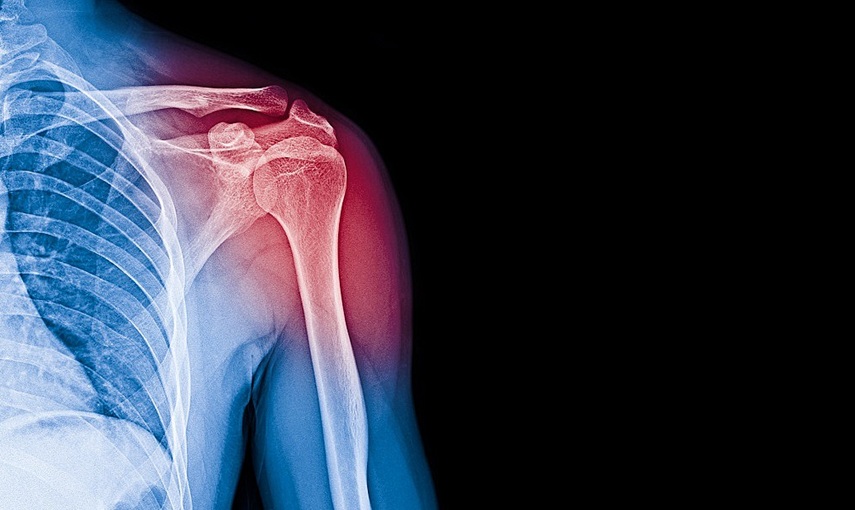

Un dolore alla spalla che non passa, fatica nei movimenti, magari uno “scatto” fastidioso ogni volta che si solleva il braccio. È così che si manifesta, spesso, una lesione alla cuffia dei rotatori, quella complessa struttura di tendini e muscoli che consente alla spalla di muoversi in tutte le direzioni.

La Società Italiana di Ortopedia e Traumatologia (SIOT) accende i riflettori su un problema molto diffuso, soprattutto dopo i 60 anni, ma non raro neanche tra i più giovani. In Italia, secondo i dati SIOT, circa il 30% degli over 60 presenta alterazioni o rotture della cuffia dei rotatori, con una quota crescente anche tra i più giovani, in particolare tra gli sportivi o chi svolge lavori particolarmente usuranti.

Non è quindi solo una questione di età: “Una cuffia malandata può essere il risultato di una degenerazione progressiva legata al tempo, al fumo o alla postura sbagliata, ma anche ad un trauma improvviso, come una caduta o un movimento sbagliato – spiega la dottoressa Erika Viola, consigliere SIOT e direttore della Uoc di Ortopedia e traumatologia all’Asst Cremona, Ospedale di Cremona –. Sport praticati senza preparazione, inoltre, possono aumentare il rischio, così come una familiarità per questo tipo di patologie. La degenerazione e le lesioni della cuffia non sono sinonimi, ma spesso si succedono e vanno valutate caso per caso: non sempre serve operare, ma è importante riconoscere i segnali d’allarme e intervenire con le giuste terapie”.

Dolore alla spalla, soprattutto notturno o durante i movimenti sopra la testa, debolezza, difficoltà nei movimenti, sensazioni di “scatto” o “schiocco” sono sintomi da non sottovalutare. “Le lesioni della cuffia dei rotatori – aggiunge Erika Viola – possono essere anche molto dolorose, a seconda della loro posizione, dimensione e dell’età del soggetto. È importante non sottovalutare il dolore alla spalla, soprattutto se persiste o peggiora nel tempo. La diagnosi inizia con una visita accurata, supportata da esami mirati: non sempre una lesione visibile è la vera causa dei sintomi”.

“La chirurgia – evidenzia il professor Pietro Simone Randelli, presidente SIOT, ordinario di Ortopedia all’Università degli Studi di Milano e direttore della Clinica Ortopedica dell’Istituto Gaetano Pini – è indicata nei casi di dolore persistente e debolezza marcata, ma molte lesioni, specie se parziali, possono essere gestite con infiltrazioni mirate, fisioterapia e controlli periodici. Le lesioni anteriori, di grandi dimensioni o in soggetti fragili vanno valutate con attenzione, perché possono progredire più facilmente. In pazienti selezionati l’intervento chirurgico, solitamente artroscopico, rappresenta un’opportunità per il ritorno all’attività sportiva e ad una spalla non dolente nella vita quotidiana”.